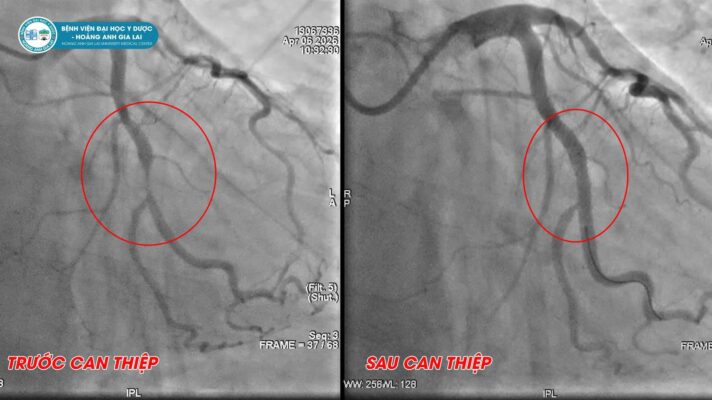

Không chỉ là nơi thực hiện các kỹ thuật can thiệp tim mạch hiện đại, Đơn nguyên Can thiệp nội mạch Bệnh viện Đại học Y Dược – Hoàng Anh Gia Lai còn là nơi mỗi người bệnh được tiếp cận với sự chăm sóc tận tâm, trách nhiệm và đầy nhân văn. Ở đó, từng ca bệnh không chỉ là một quy trình điều trị, mà là hành trình giữ lại sự sống, gìn giữ những nhịp tim và trao thêm cơ hội cho người bệnh trở về với gia đình.